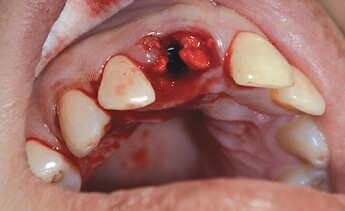

The patient presented with a failing tooth #8. After extraction, the socket shape resembled a triangle. Because of the round shape of the dental implant, there were gaps between the implant body and the alveolus which required grafting.

After the tooth was extracted, the site was thoroughly curetted. A pilot drill was used to begin the osteotomy, which was enlarged to the correct size for the implant. Prior to placing the implant, OsteoGen strip alloplast was re-hydrated with sterile saline and then placed in the socket against the wall adjacent to the gap. Hahn™ Tapered Implant (Glidewell Direct; Irvine, Calif.) was driven into place, and the graft material filled the gap. A healing abutment was placed and the site sutured with a Reli® REDISORB® PRO PGA 4-0 suture.